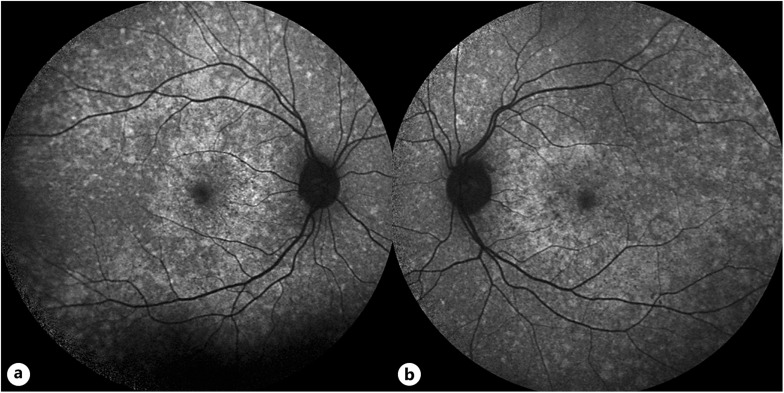

Case presentation: Subject of this case report is a 33-year-old woman, who was examined at the Department of Ophthalmology at Medical University of Graz. A thorough ophthalmological examination was conducted, detailed medical and family history acquired, and genetic testing performed. Best corrected visual acuity was 20/20 on both eyes; however, impaired binocular vision associated with intermittent exotropia was found. Furthermore, dilated fundoscopy showed an unusual, hypopigmented spotted retinal phenotype. Fundus autofluorescence showed multiple hyperfluorescent spots corresponding with the spotted retinal appearance. Genetic testing revealed a novel variant in the gene COL11A1. No other ocular abnormalities which are associated with COL11A1 were found.